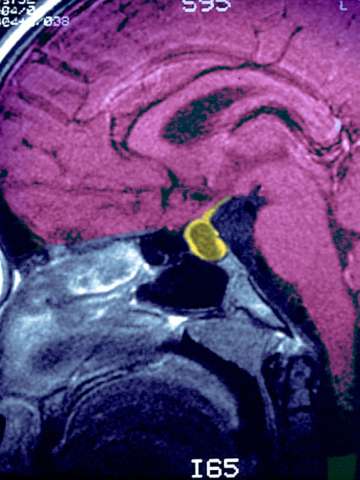

Expert care starts with an accurate diagnosis. Our pituitary specialists use the most advanced technologies available to deliver the right diagnosis the first time. We specialize in:

Advanced diagnostics for pituitary tumors

Our experts diagnose even the most complex pituitary tumors using sophisticated equipment and unapparelled expertise. We provide: